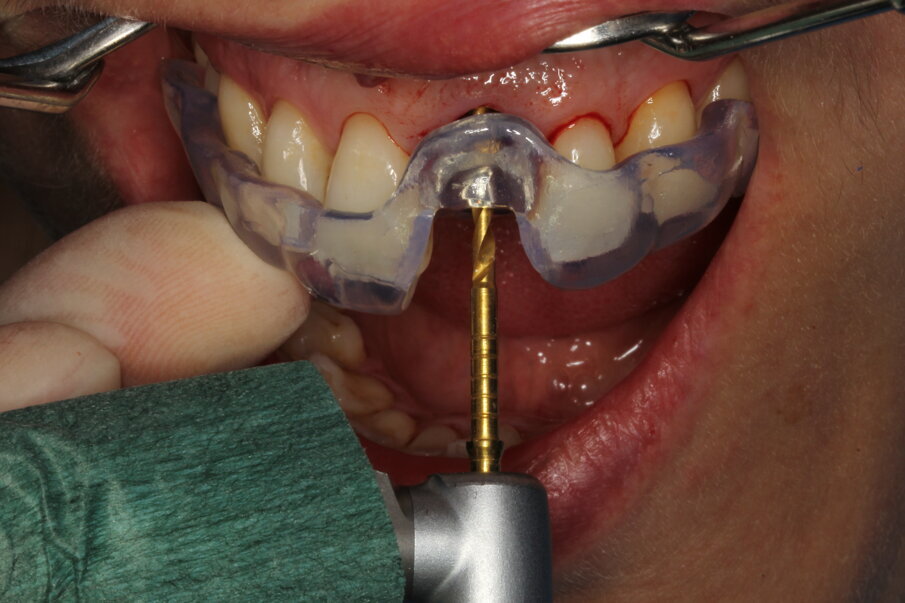

Local anaesthesia was performed with 2% mepivacaine with 1:100,000 adrenaline. Preventative antibiotic therapy with amoxicillin (1 g, b.d. for five days) was prescribed, aided by use of a 0.2 % chlorhexidine mouthrinse three times a day for one minute. The tooth was extracted and the sulcular epithelium removed with diamond burs. The milled surgical template (Figs. 12 & 13) served as a guide for the first 2 mm diameter pilot drill (Fig. 14). Thus, the planned depth, position and angulation of the osteotomy were obtained. The drill sequence was completed freehand, using tapered 3.0 and 3.4 mm drills. A Neoss Pro- Active Tapered Implant of 4 mm in diameter and 13 mm in length was inserted flush with the mesial/palatal/distal bone, motor driven up to a torque of 50 Ncm and then with a manual wrench (Fig. 15). The correct position of the internal hex was verified by checking the references on the implant driver, which ideally points in the buccal direction. Resonance frequency analysis with Penguin RFA (Integration Diagnostics Sweden) determined an ISQ value of 73/76. At this stage, a Neoss Esthetic Healing Abutment with a ScanPeg was connected to the implant (Fig. 16). A flap was then raised after a vertical incision of the frenulum and the expected buccal exposure of the implant neck was evident. Autogenous bone harvested from the drills was positioned directly on the implant surface (Fig. 17), followed by a bone substitute on top of it and on the buccal cortical bone (Fig. 18). This material was covered with a resorbable membrane (Fig. 19). The mobilised flap was then repositioned by rotating it coronally and fixed with single sutures (Fig. 20). The removable partial denture was adapted and delivered (Fig. 21). An immediate postoperative CBCT scan of 60 x 60 mm was performed, and it confirmed a perfectly centred implant position (Figs. 22 & 23).